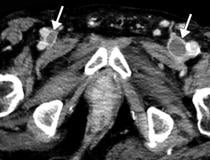

This photo gallery shows the variety of radiological presentations of COVID-19 (SARS-CoV-2) in medical imaging, including computed tomography (CT), radiograph X-rays, ultrasound, echocardiograms and magnetic resonance imaging (MRI). The radiology images show examples of typical COVID pneumonia in the lungs and the numerous complications the virus causes in the body in multiple organs, including the brain, kidneys, heart, abdomen and vascular system.